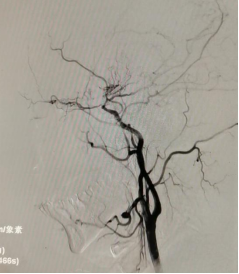

烟雾病是一种罕见的慢性闭塞性脑血管疾病,其病因目前尚不明确。该疾病的主要表现为颈内动脉(ICA)末端进行性闭塞伴颅底异常烟雾状血管网形成,因其在脑血管造影上形似“烟雾”而得名,多发于青壮年,具有极大的危害性。多数患者因出现临床症状而就医,烟雾病的临床表现主要包括脑梗死、脑出血、癫痫发作、神经功能障碍等。检查方式主要有磁共振、CTA等,而最佳的检查方法为DSA脑血管造影术。

此次的女性患者李某、尹某以及男性患者李某,均在1月前因脑梗塞或蛛网膜下腔出血而进行了DSA检查,确诊为烟雾病。他们通过多方了解,找到了东方总院神经外科的张德辉院长。张院长凭借丰富的搭桥手术经验,详细解释了烟雾病的病因、临床表现、鉴别方式、治疗方式,并介绍了与鼓楼医院神经外科的合作平台及杨咏波教授在烟雾病搭桥手术上的高超技术和丰富经验。家属们听后毫不犹豫地选择在东方总院神经外科进行搭桥手术。经过手术,三位患者恢复良好,无并发症,术后第二天便开始下床活动,并在一周后康复出院。

▲三台烟雾病搭桥手术进行中,杨咏波教授在进行搭桥手术